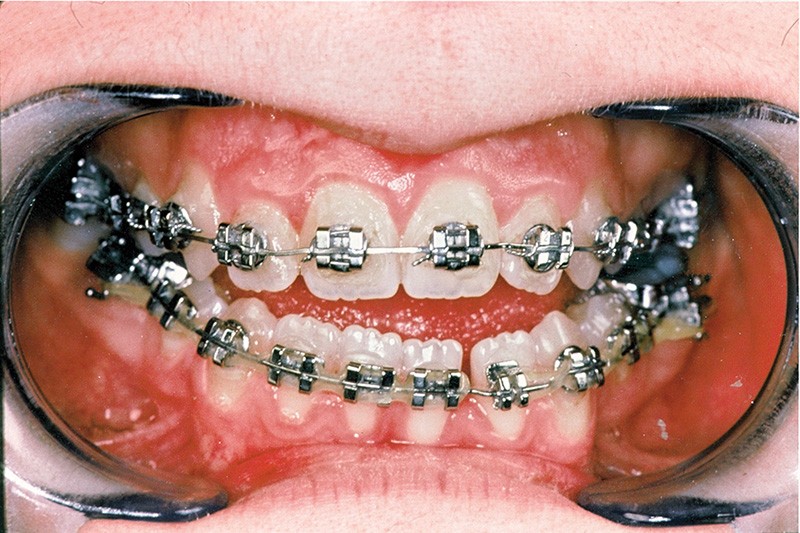

• une préparation orthodontique préchirurgicale avec extraction des quatre premières prémolaires qui a assuré la correction de l’encombrement, la décompensation de la malocclusion et l’harmonisation des formes d’arcades (fig. 4 et 5),